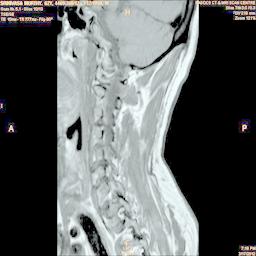

In order to show the proposed method in more detail, the algorithm is tested with other test images. The first row of Fig. 6 shows the original MRI image of thoracic spine with different views. The second row of Fig. 6 shows the same image enhanced using histogram equalization. Third row of Fig. 6 presents the MSR based enhancement scheme. Fourth row of Fig. 6 indicates Chao’s method of image enhancement. Finally, the reconstructed images using the proposed method is shown in fifth row of Fig. 6. Again, it can be seen from the results presented that the image enhancement using the proposed method is superior compared to other methods. This is evident from the image quality assessment presented in Table 1 using AWE and DWE.